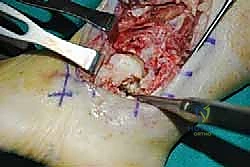

Exposure of lateral ankle and subtalar joints. Note the fragmentation of the inferior surface of the talar body ( TECH FIG 8 ).

TECH FIG 8 • Lateral approach to ankle and subtalar joint after distal fibular resection.